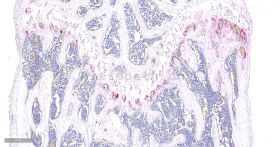

TRAP染色:TRAP 染色是用于检测骨组织、骨细胞中特征物质的染色,使破骨细胞呈红色,背景呈绿色或蓝色。抗酒石酸酸性磷酸酶(TRAP)为破骨细朐的标志酶,特异地分布于破骨细胞中,为破骨细胞所特有,通常作为鉴别破骨细胞的重要标志物。在含酒石酸的酸性条件下,TRAP 能将萘酚 AS-BI磷酸盐水解,产生的萘酚 AS-BI 立即与 fast red 或六偶氮副品红结合,在酶活性部位形成不溶性的红色染料,通过观察红色染料的形成可间接了解酸性磷酸酶的活性,进一步鉴别及分析破骨细胞的状态。

染色结果:破骨细胞呈红色,背景呈绿色或蓝色。